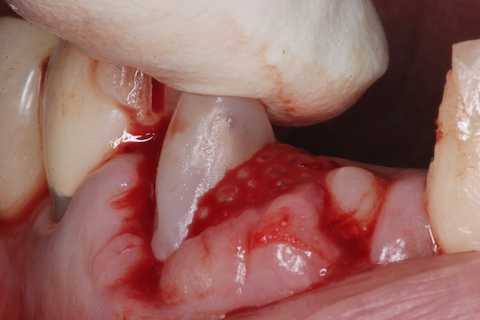

普通にズブズブと抜歯窩に再建した歯根を挿入する。